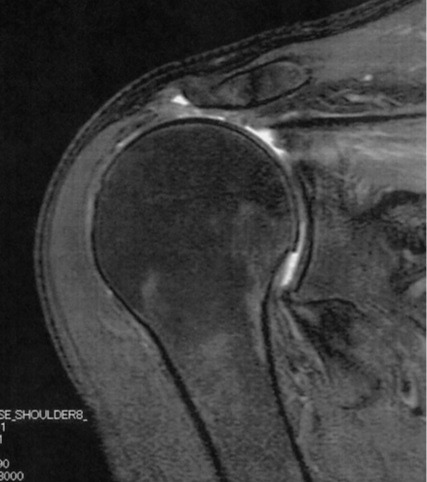

リバース症例の術前MRI所見

広範囲断裂

Goutallier分類Stage3

腱板の断端がみえないほど大きな断裂で脂肪変性もすすんでいます。